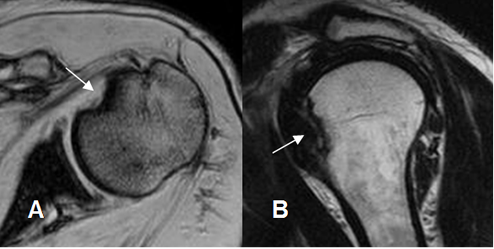

Fig 50 B. Bankart óseo.

A: ArtroRM axial en STIR y B: ArtroRM sagital en STIR. Defecto del reborde anterior inferior de la glenoides y el labrum articular, por lesión de Bankart óseo. (Flechas).